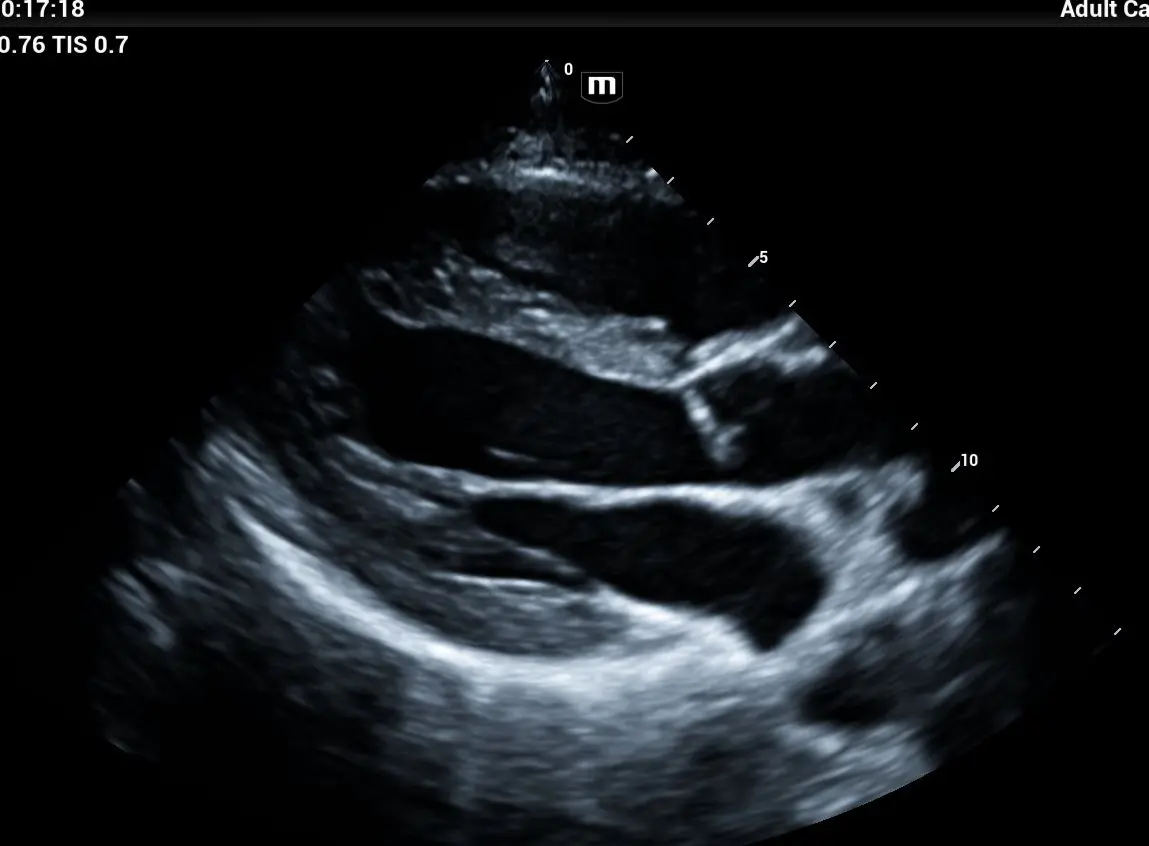

¿Qué es el Ecocardiograma ?

El ecocardiograma es un estudio de imagen cardíaca que utiliza ultrasonido para obtener imágenes en tiempo real del corazón. Es una de las principales herramientas diagnósticas en cardiología porque no es invasivo, determina cardiopatías, insuficiencia cardiaca , el flujo sanguíneo , enmerdades valvulares.

¿Qué es el Ecocardiograma Doppler con Strain?

Es una evaluación cardiovascular de alta precisión que permite analizar el funcionamiento estructural y mecánico del corazón en tiempo real, midiendo no solo la anatomía, sino también la contractilidad y deformación miocárdica (Strain). Con la tecnología Philips Affinity 70, LIB Laboratorios ofrece un estudio de nivel hospitalario, ideal para la detección temprana de enfermedades cardíacas (insuficiencia, Valvulopatías, Fibrosis, Isquemias, Amiloidosis…) y el seguimiento de tratamientos farmacológicos (Cardiotoxicidad).

Ecocardiograma Pediátrico

Valoración estructural y funcional del Corazón en niños Consulta con Especialista Cardiologo Certificado: 600